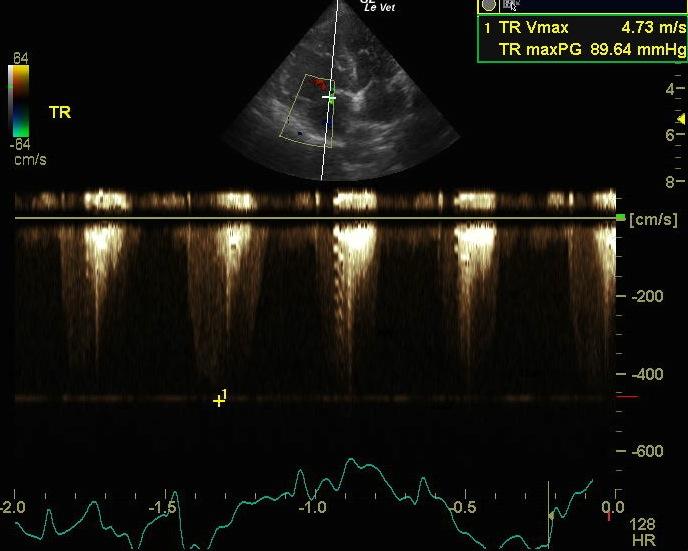

The left ventricular cavity is small in diastole (1.6 cm) and systole (1.0 cm) with a normal fractional shortening (37 %). There is flattening of the interventricular septum in systole, consistent with right ventricular hypertension. The left ventricular walls are relatively hypertrophied (0.65 cm septal wall and 0.65 cm free wall). The right ventricle appears markedly hypertrophied, and the right atrium appears moderately enlarged in size. The main pulmonary artery appears significantly enlarged in comparison to the aorta. There is moderate tricuspid regurgitation on Doppler exam with the jet directed toward the aorta. The velocity is also markedly increased to 4.73 m/sec, describing a pressure gradient of 90 mmHg, consistent with pulmonary hypertension. The heart rate is measured at 124 to 149 BPM and a regular sinus rhythm is seen on an ECG run during the exam.